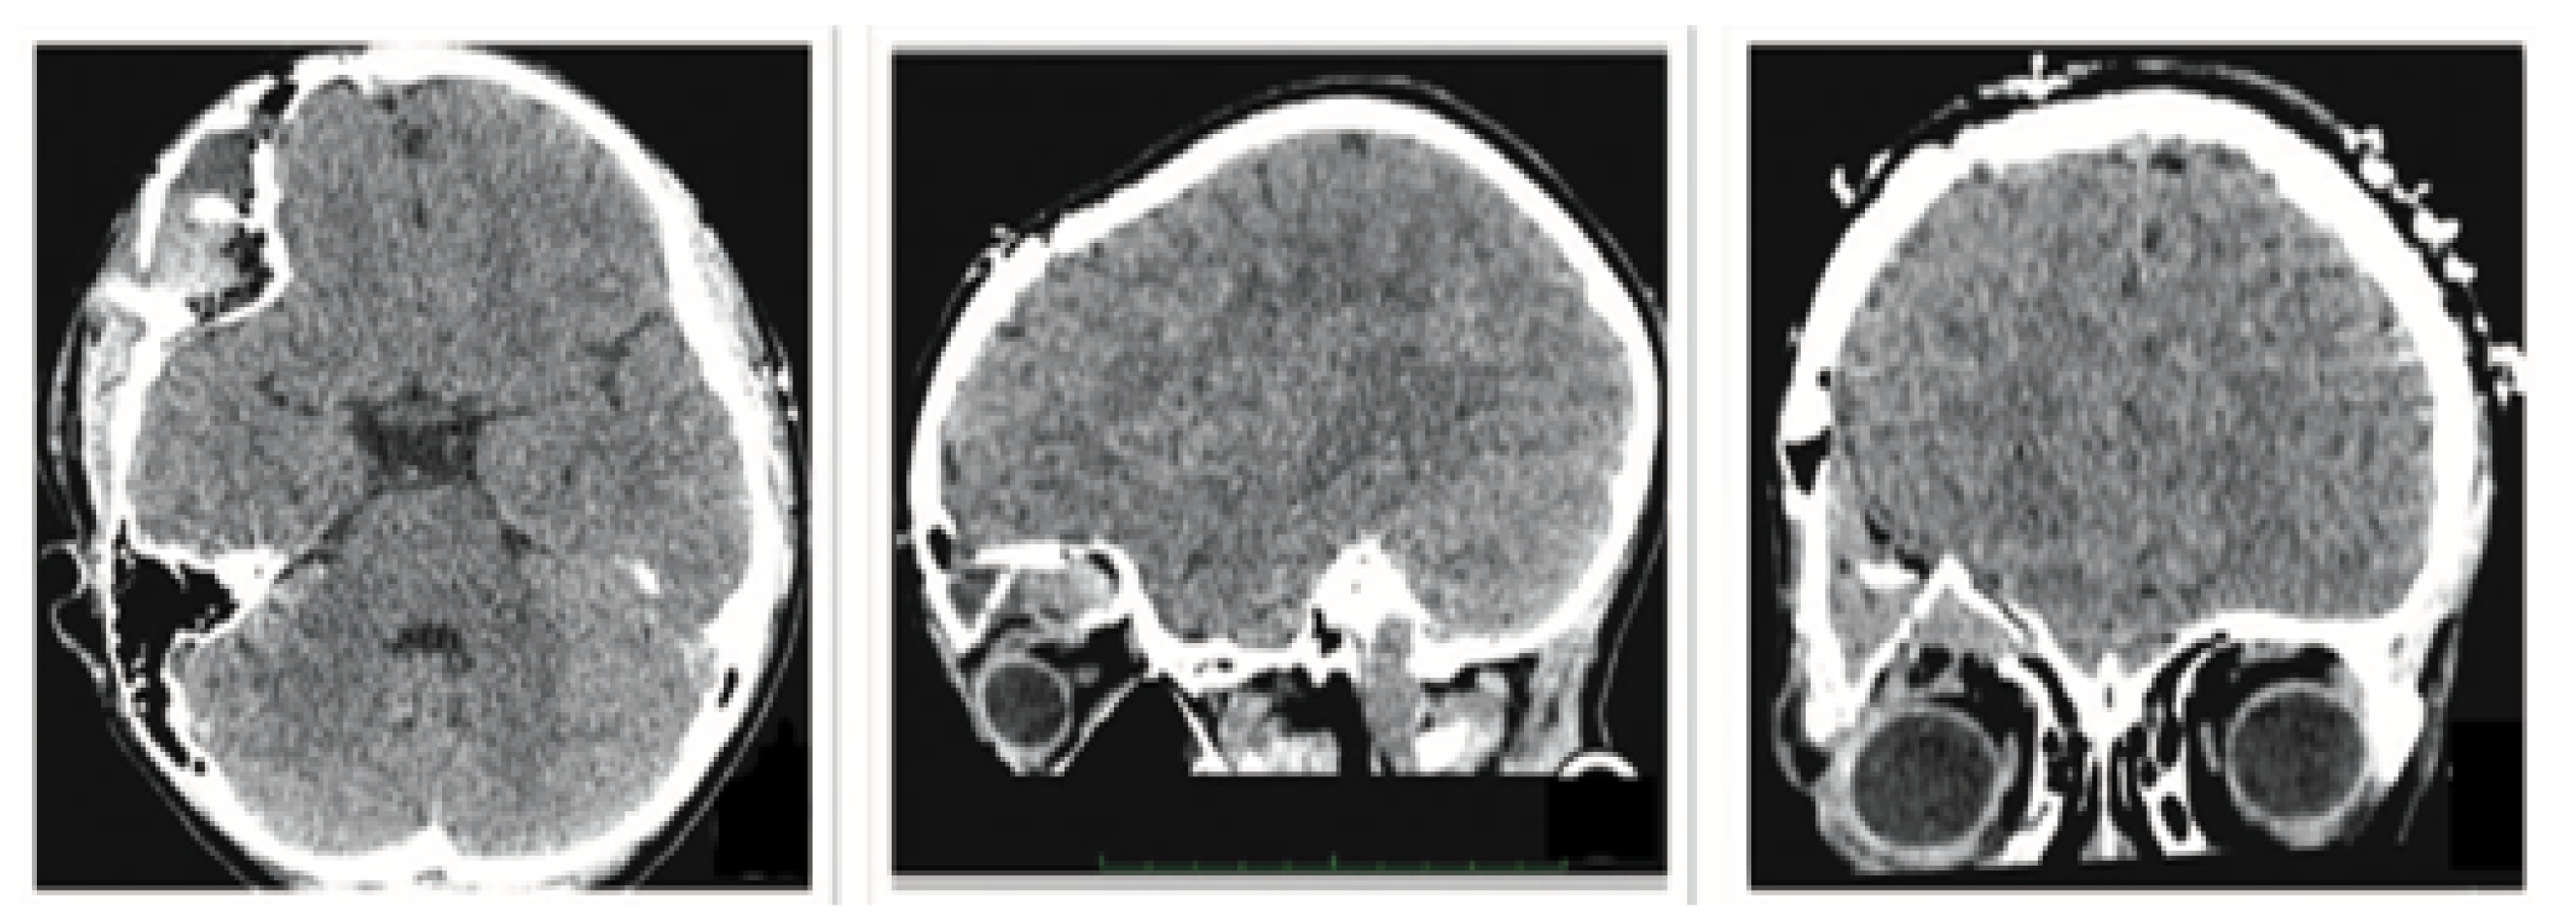

3.7.1. Diagnosis and Analysis

3.7.2. Surgical Planning